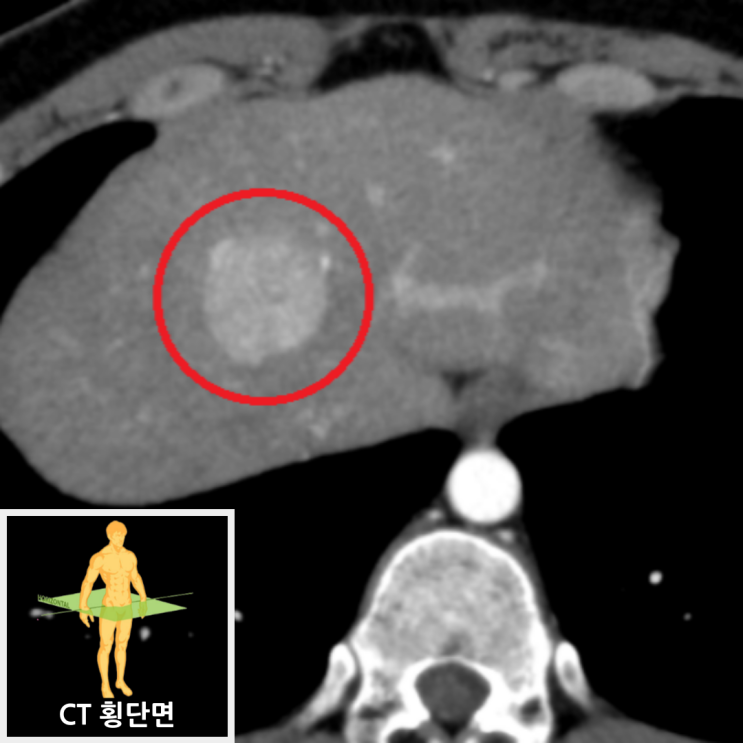

복부CT에서 중간 간엽에 3cm크기의 고음영 결절이 보였으며, 이 결절은 지연기 영상에서 간 실질과 동음영을 보였습니다. 추가적 확인을 위해 MRI를 촬영한 결과, CT상 결절은 MRI 20분 지연 영상에서 간 실질보다 고신호로 보이고 있으며, 가운데에 섬유증 반흔이 보여 국소결절과형성으로 판단되었습니다.

• 복부CT: 간 중간 엽 3cm 고음영 결절 복부CT: 간 중간 엽 3cm 고음영 결절